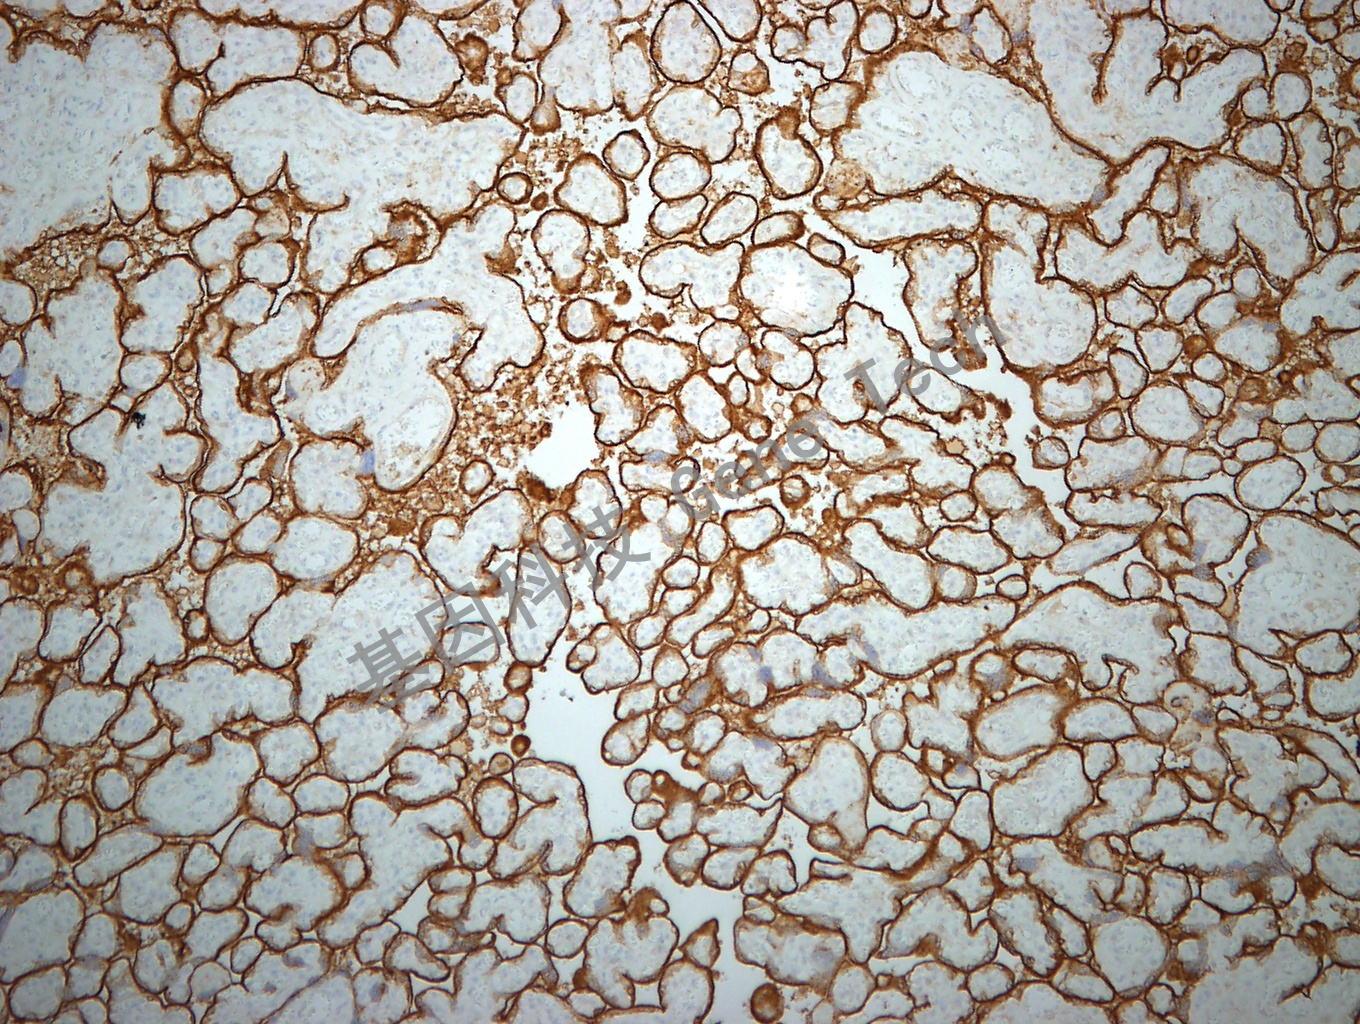

胎盘石蜡切片,用 CD71(GT2143)染色,细胞膜/细胞浆阳性,DAB显色。(10×)

胎盘石蜡切片,用 CD71(GT2143)染色,细胞膜/细胞浆阳性,DAB显色。(40×)